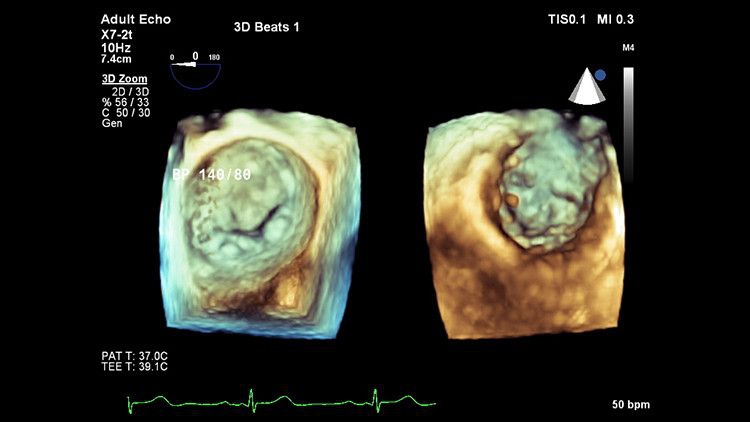

Система EPIQ CVx представляет собой специализированное решение для ультразвуковых исследований сердца, которое значительно улучшает функциональные возможности. Это способствует повышению качества медицинской помощи путем увеличения вычислительной мощности, обеспечения исключительного качества визуализации с более высокой четкостью и резкостью, повышения эффективности исследований, а также использования новой технологии надежного и воспроизводимого количественного анализа данных AIUS.

Качество изображения на EPIQ CVx

Монитор с технологией OLED обеспечивает четкую визуализацию анатомии сердца за счет расширенного динамического диапазона и улучшенного контраста. Каждый может увидеть изображение с высокой четкостью даже в нетрадиционных условиях, таких как операционная.

Автоматизация для robust, доказанного воспроизводимого сердечного квантификации и в 2D и в 3D

Система быстро и надежно осуществляет количественную оценку 2D-деформаций ЛВ, ЛА и ПЖ благодаря интеграции с TOMTEC. Полная количественная оценка в 3D предоставляется для объемов и функциональной оценки ЛВ, ЛА и ПЖ с использованием динамической модели сердца. Анализ митрального клапана также осуществляется с помощью динамического анализа MV.